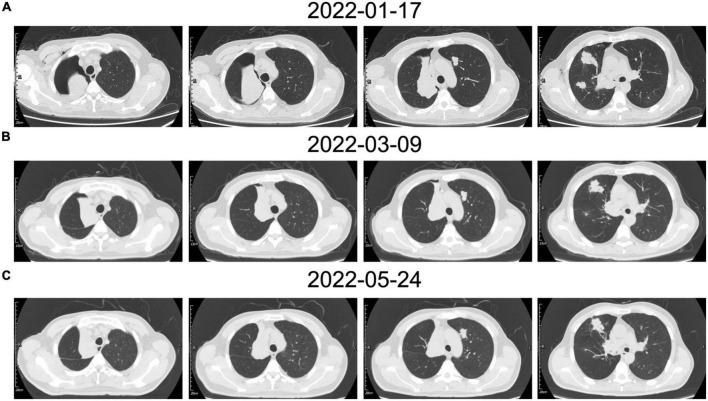

Pulmonary epithelioid hemangioendothelioma (PEH) is a rare vascular tumor of endothelial origin with low- to intermediate-grade malignant potentials. Since there is no characteristic clinical or biological marker available for PEH, most cases require a surgical lung biopsy for diagnosis. To date, although some patients with PEH reported in the literature were diagnosed through bronchoscopic biopsy, most of the patients still underwent surgical lung biopsy for confirmation. In this case report, we present a rare case diagnosed as PEH through endobronchial biopsies due to the presence of an intraluminal mass that blocked the trachea and caused atelectasis in the right upper lobe. Moreover, since surgery was not appropriate for this patient with unresectable bilateral multiple nodules, we adopted genetic analysis using NGS to provide a guide for personalized treatment. Then, based on the NGS results, the patient was treated with anti-PD-1 mAb and sirolimus for 1 year and has been stable in a 1-year follow-up examination.

肺上皮样血管内皮瘤(PEH)是一种罕见的起源于内皮的血管肿瘤,具有低至中度恶性潜能。由于目前尚无针对PEH的特征性临床或生物学标志物,大多数病例需要进行手术肺活检以明确诊断。迄今为止,尽管文献报道的一些PEH患者是通过支气管镜活检确诊的,但大多数患者仍需接受手术肺活检以进行确诊。在本病例报告中,我们介绍了一例罕见病例,该病例因腔内肿物阻塞气管并导致右上叶肺不张,通过支气管内活检确诊为PEH。此外,由于该患者双侧多发结节无法切除,手术并不适宜,因此我们采用二代测序(NGS)进行基因分析,为个性化治疗提供指导。然后,根据NGS结果,该患者接受抗程序性死亡受体1(PD-1)单克隆抗体和西罗莫司治疗1年,在1年的随访检查中病情一直稳定。